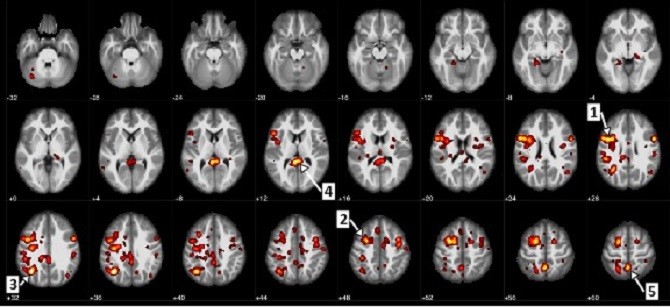

Bức ảnh chụp MRI cho thấy các phân tích, thống kê quan trọng về các dòng máu lưu thông trong não bộ (ảnh: IBM).

Nhóm nghiên cứu đầu tiên đã đào tạo mạng lưới thần kinh của hệ thống với bộ dữ liệu ảnh chụp MRI của 95 người từ Mạng lưới Nghiên cứu Chức năng Thông tin Y sinh (Function Biomedical Informatics Research Network), bao gồm các bản quét của cả hai nhóm bệnh nhân bị mắc chứng tâm thần phân liệt và nhóm được kiểm soát sức khỏe.

Những bức ảnh này minh họa các dòng lưu thông của máu qua các bộ phận khác nhau của não bộ khi bệnh nhân hoàn thành một bài kiểm tra đơn giản liên quan tới âm thanh. Từ dữ liệu này, mạng lưới thần kinh được kết hợp lại thành một mô hình tiên đoán về khả năng mắc chứng tâm thần phân liệt của một bệnh nhân, dựa trên sự lưu thông của máu trong não bộ của họ. Nó đã có thể phân biệt được chính xác đến 74% kết quả giữa nhóm được kiểm soát và những người mắc chứng tâm thần phân liệt.